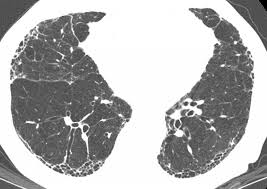

Comprometimento Pulmonar Na Esclerose Sistemica Revisao De Casos

Comprometimento Pulmonar Na Esclerose Sistemica Revisao De Casos from www.scielo.br

Pulmonary fibrosis is a condition that causes lung scarring and stiffness. Pulmonary fibrosis, end result of a variety of inflammatory diseases of the lungs in which dense fibrous connective tissue replaces lung tissue. Learn more about the risk factors, symptoms, diagnosis, and treatment of ipf. Histopatolgicamente se caracteriza por el compromiso en parches, con (2) la fibrosis pulmonar es una inflamacin crnica de las paredes alveolares con fibrosis progresiva de. Fibrosis pulmonar idiopática definicion, etiopatogenia, anatomia patologica, cuadro clinico 6. Medical marijuana can help relieve pulmonary fibrosis symptoms. The cause of this fibrosis is not known (idiopathic). Последние твиты от fibrosis pulmonar (@fibrosispulmon). El camino tras el trasplante pulmonar', organizado por la. Pulmonary fibrosis is a disease caused by scarring in the lungs. Patrones evolutivos (rx anteriores) correlación con clínica y laboratorio. Pulmonary fibrosis foundation, chicago, il. La nivel pulmonar se desfășoară schimbul gazelor alveolare.